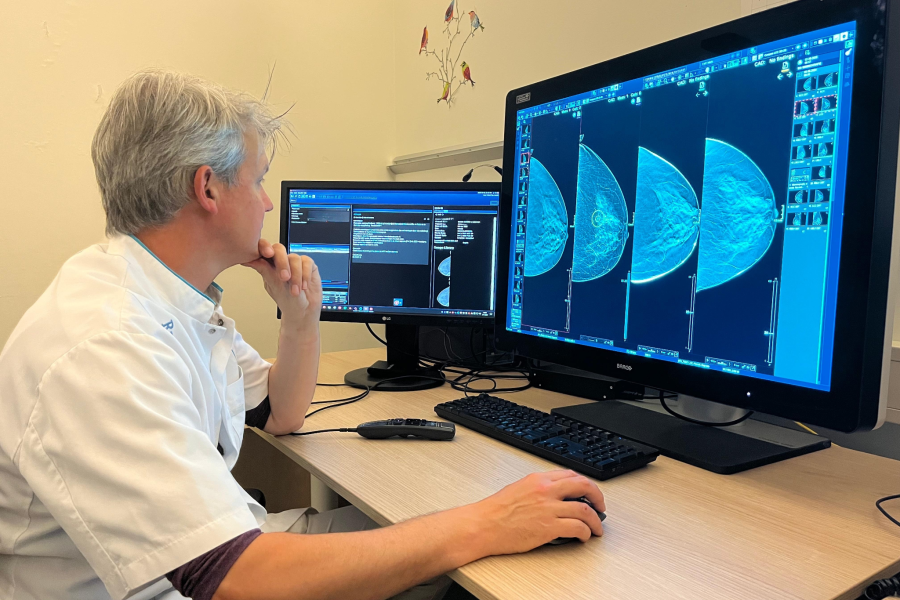

AI beoordeelt ook Nederlandse mammografie beter dan radioloog

Computer kan tweede radioloog vervangen bij borstkankerscreening AI spoort ook in Nederland vaker en eerder tumoren op in het screeningsprogramma voor borstkanker. Die tumoren kunnen dan in een eerder stadium behandeld worden. Dat tonen onderzoekers onder leiding van het Radboudumc in The Lancet Digital Health. Inzet van AI kan de werkdruk verminderen en miljoenen euro’s […]